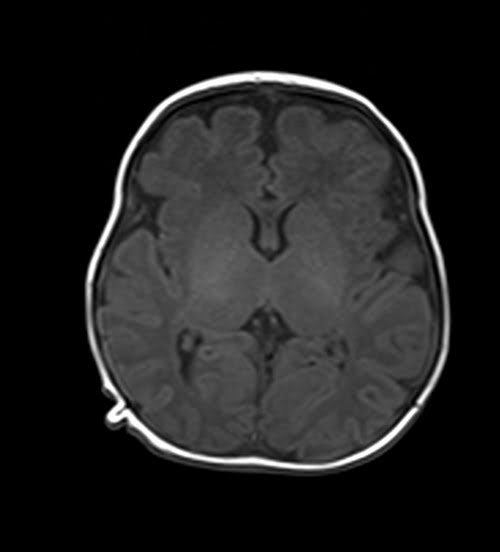

MRI pediatric brain axial T1 images